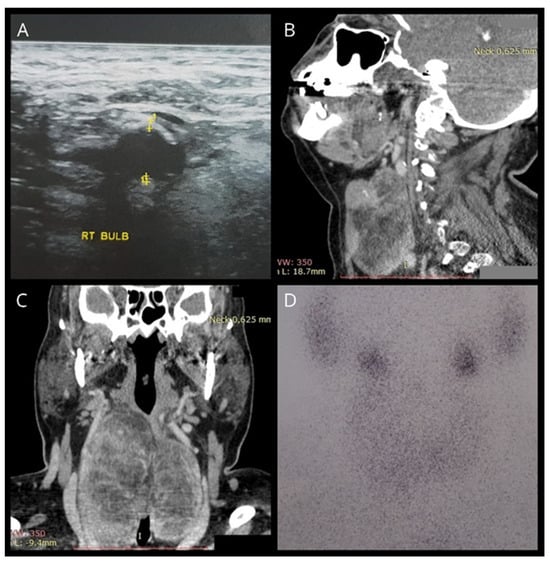

| Present Study | F/61 | Neck swelling, dyspnea, dysphagia | Normal | Yes | U/S: enlarged thyroid gland with hyperechoic areas. CT: large size of gland, diffuse low parenchymal density, and retrosternal extension. Tc99m scintigraphy: low uptake diffusely. | Diffuse goiter | Total thyroidectomy | NS | Fatty infiltration of thyroid, degeneration of follicles | NS | Dead–after 3 years (because of kidney failure) |